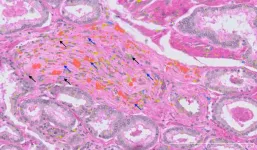

The research team, led by Professor Alexander Swarbrick, Co-Director of the Cancer Ecosystems Program and Lab Head at Garvan, analysed tissue from 24 patients recently diagnosed with early-stage prostate cancer. The samples were drawn from the Garvan St Vincent’s Prostate Cancer Biobank – the largest in the southern hemisphere, with contributions from more than 16,000 patients over three decades. The team then used advanced single-cell RNA sequencing to examine the genetic activity of every single cell in a tissue, and spatial transcriptomics to map their exact locations in the tumour landscape.

This resulted in a comprehensive atlas, identifying 11 major cell types, 50 minor subtypes, and numerous cell state classifications within prostate cancer tissue. This level of detail provides the global research community with an invaluable resource for studying how the tumours form and opportunities to design new therapeutics.

Standard diagnosis relies on visually identifying structural irregularities in cells under a microscope. However, this study revealed that the progression from healthy prostate tissue to cancer involves multiple cellular states that are invisible. The researchers found that many epithelial cells – the cells that line organs and are where most cancers originate – showed early genomic alterations, even in tissue that appeared ‘normal’. This suggests that molecular testing could one day be used to detect these invisible warning signs, potentially allowing for diagnosis before the cancer can be seen by a pathologist.